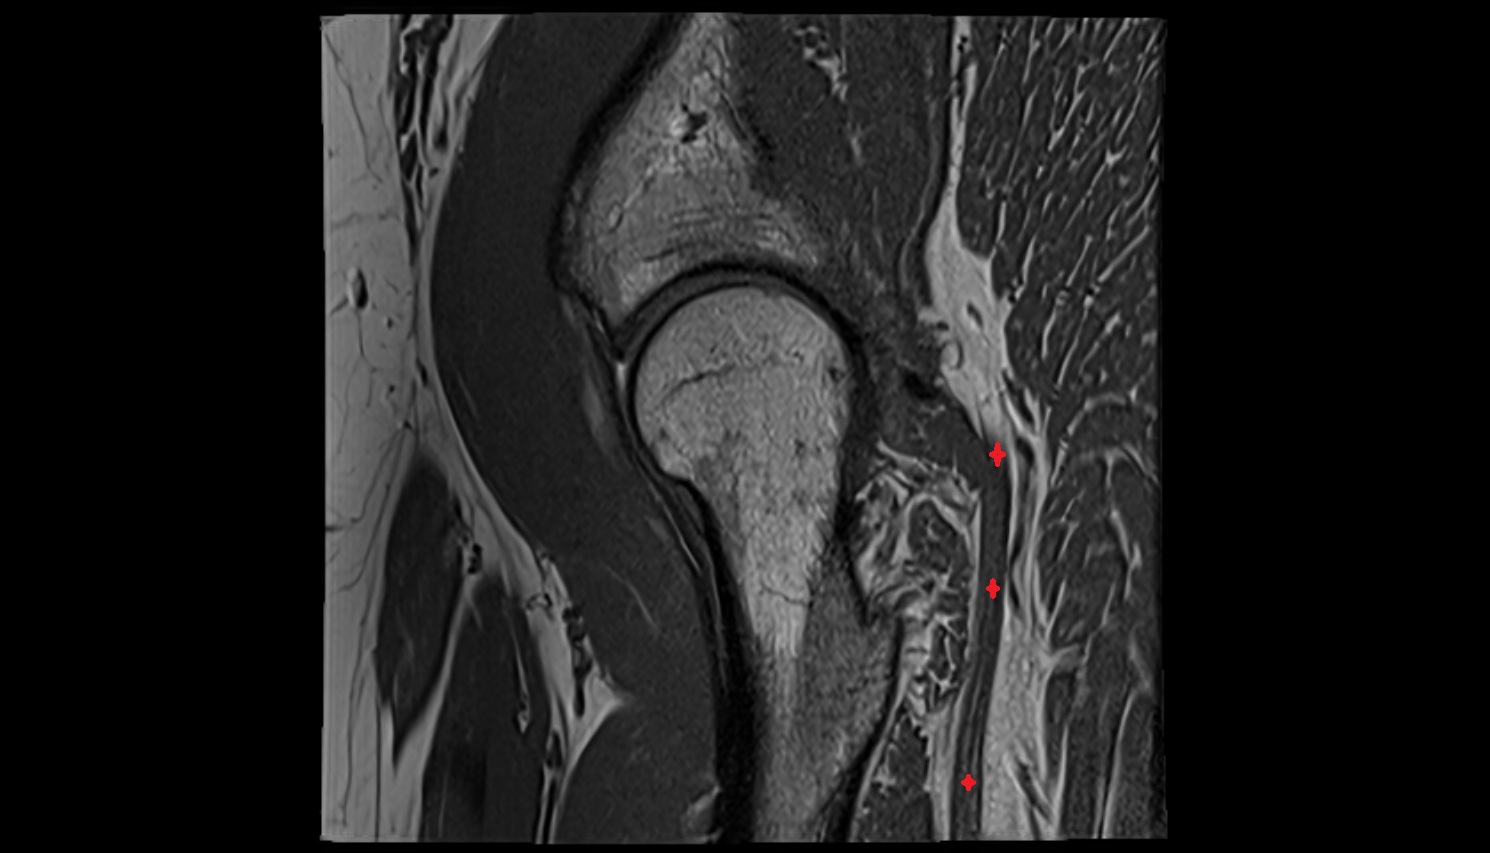

- Iliopsoas tendon